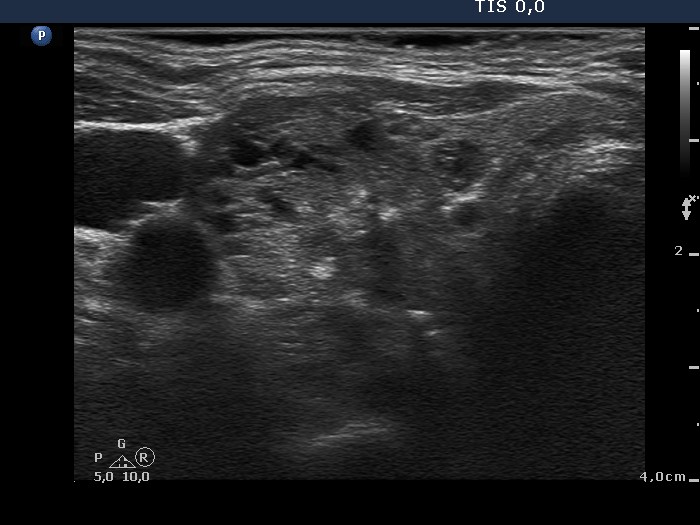

Benign hyperplastic nodule (histological diagnosis) - case 653

Note the linear figures in the back wall of the cystic areas. The ventral solid area of the nodules contains both hyperechogenic lines and granules; therefore these figures correspond to connective tissue. It is ambiguous whether the echogenic figures in the dorsal solid area (right image) are presentations of connective tissue or posterior acoustic enhancements but the former seems to be more likely.